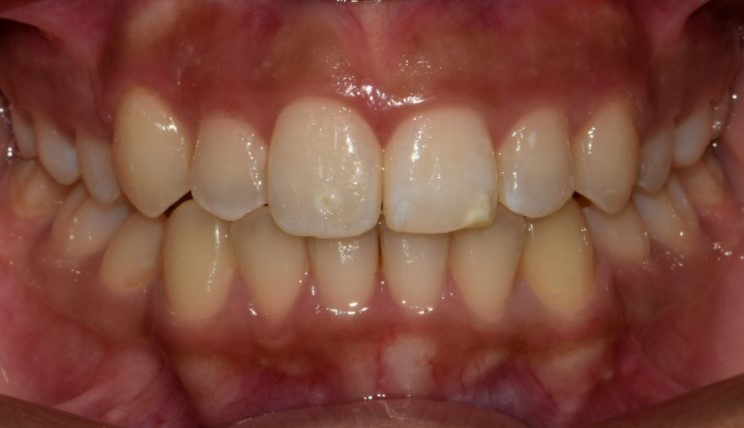

Phase I Treatment

Interceptive treatment for young patients (6-10 years old): Early treatment can be in a patient’s best interests if their problem is one that could become more serious over time if left untreated. - Intercept the developing problem; Eliminate the cause; Guide the growth of facial and jaw bones; Provide adequate space for incoming permanent teeth.

Patient Information:

Age: 9

Gender: Male

Invisalign Treatment Option: Invisalign Teen with MA

Total Treatment Time:

13 months